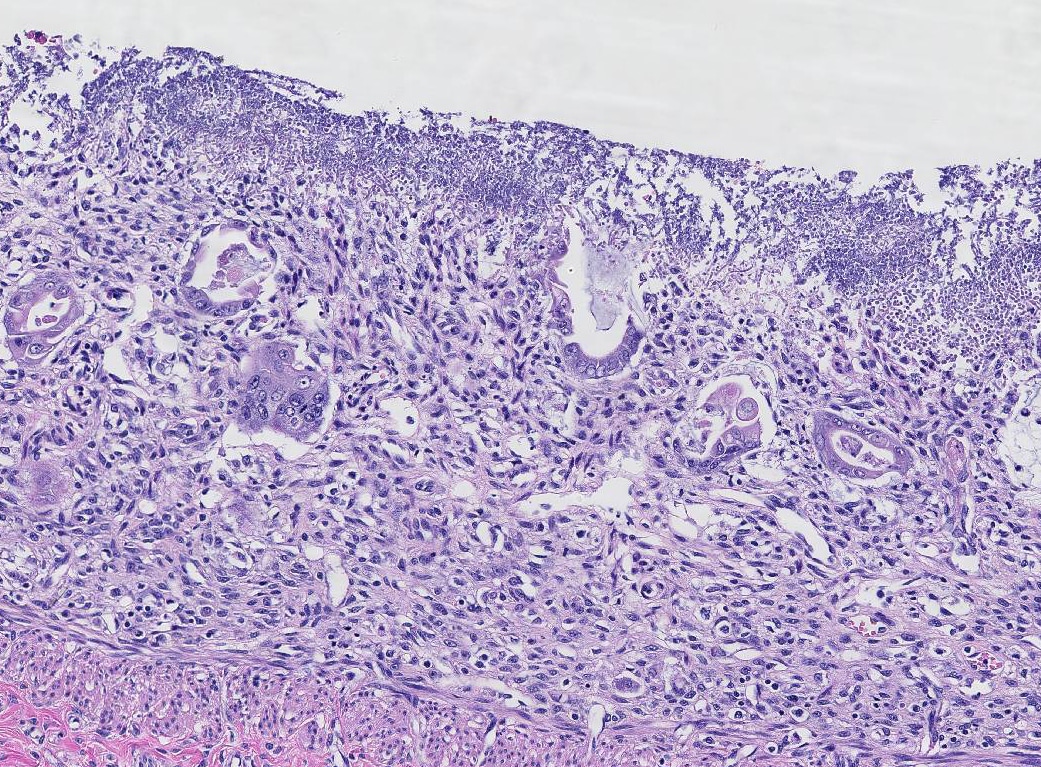

Парвовірус дуже стійкий у зовнішньому середовищі. Він зберігається на землі, у фекаліях, на взутті, лапах, предметах догляду — навіть при високих температурах чи впливі дезінфекторів. Найпоширеніший шлях зараження — фекально-оральний. Собака може підхопити вірус, просто понюхавши або лизнувши заражену поверхню. Інфікування відбувається миттєво: вірус потрапляє в організм, атакує клітини кишківника та імунної системи, спричиняючи запалення, некроз тканин, діарею з кров’ю, блювання та загальну інтоксикацію. Важливо розуміти, що навіть повністю домашній пес, який ніколи не виходить на вулицю, може заразитися — через господарів, які приносять вірус на одязі, руках або взутті.

Цуценята у віці від 6 тижнів до 6 місяців є найбільш незахищеними. У них ще не сформована повноцінна імунна відповідь, а кишківник надзвичайно чутливий. Якщо цуценя не вакциноване або не пройшло повний курс щеплень, вірус розвивається дуже стрімко. Найстрашніше — іноді господар помічає симптоми надто пізно. У перші 12–24 години після зараження цуценя може виглядати просто трохи млявим, але вже через добу розвивається блювання, пронос (часто з кров’ю), повна відмова від їжі й води. Без негайної ветеринарної допомоги смертність серед невакцинованих цуценят сягає 90%. І саме тому перше щеплення — це не «про всяк випадок», а реальний порятунок життя.

Класичні симптоми включають сильну апатію, різке зниження апетиту або повну відмову від їжі, часте блювання, рідкий пронос з домішками крові, різкий запах фекалій, підвищену температуру або, навпаки, гіпотермію, а також зневоднення. У важких випадках собака не реагує на подразники, лежить без сил, ясна стають блідими або синюватими. Симптоматика може трохи варіюватись залежно від породи, віку й загального стану імунної системи. Але головне — парвовірус не «чекає». Якщо ви помітили хоча б кілька з цих симптомів, особливо у молодої тварини — не зволікайте. Звернення до ветеринара в перші години після появи ознак може бути критичним для порятунку життя.